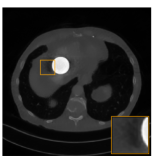

Fig. 3.2: Reconstruction from simulated data with 5 %times5percent5\text{\,}\mathrm{\char 37\relax} Gaussian noise. The contrast is enhanced to emphasize the difference in the reconstructions.

To simulate noisy data we add 5 %times5percent5\text{\,}\mathrm{\char 37\relax} Gaussian noise to the measurement data, i.e. we use yδ=y+0.05y¯δsubscript𝑦𝛿𝑦0.05¯𝑦𝛿y_{\delta}=y+0.05\cdot\bar{y}\cdot\delta where y¯¯𝑦\bar{y} is the mean of the data and δ𝛿\delta is a standard normal distributed noise term. Reconstructions using FBP, post-processing and the sparse aNETT are shown in Figure 3.2. We enhance the contrast in these images by a factor of c=1.7𝑐1.7c=1.7 using the Python Pillow library [16] to make the differences more clearly visible. The post-processing reconstruction shows some noise-like structure on parts where the image should be mostly constant, e.g. in and around the orange square. We hypothesize that these noise like structures occur because the problem adapted network 𝐔𝐔\mathbf{U} has not been trained with noise in the data domain and hence has difficulties in reconstructing these. While we could add this to the training the networks would then likely fail on different noise models, e.g. Poisson noise. Comparing this to the aNETT we see that this noise-like structure has been greatly reduced and we have to rely more on the sparsifying term of the regularization method to get noise-free reconstructions.